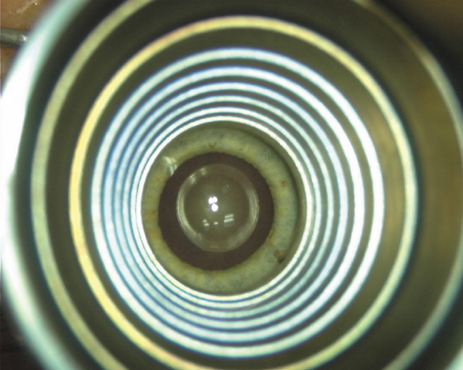

Proper centration of the incisions over the steep corneal meridian is of utmost importance. Increasing evidence supports the notion that significant cyclotorsion may occur when assuming a supine position.32 As previously noted, an axis deviation of only 15 degrees may result in a 50% reduction of surgical effect.5 For this reason, most surgeons advocate placing an orientation mark at the 12:00 or 6:00 limbus while the patient is in an upright position. This is particularly important when employing injection anesthesia wherein unpredictable ocular rotation may occur. An additional measure that may be employed to help center the relaxing incisions is to identify the steep meridian (plus cylinder axis) intraoperatively using some form of keratoscopy. The steep meridian over which the incisions are to be placed corresponds to the shorter axis of the reflected corneal mire. A simple handheld device such as the Maloney (Storz, Katena) or Nichamin (Mastel Precision) keratoscope works well, or a more robust and well-defined mire may be obtained through an elaborate microscope-mounted instrument such as the Mastel Ring of Light (Mastel Precision). Another common way in which the steep meridian is marked utilizes a Mendez Ring or similar degree gauge that is aligned with the previously placed limbal orientation mark, and the cylinder axis is then located on the 360-degree gauge.

Case 1 is a 68-year-old male who presented for right cataract surgery. His refraction was −1.00 +2.25 × 80 and was recorded as reliable, consistent with his modest cataract density. Keratometry readings were 44.75 × 75 and 43.00 × 165. Corneal topography confirmed slightly more than 2.00 D of regular and slightly oblique cylinder. Consulting the nomogram, a plan was devised for a pair of LRIs to be centered over the 75-degree axis, with each incision delineating 45 degrees of arc. A single plane phaco incision was used and maintained at a size of less than 3.2 mm (Figs. 811).

Fig. 10. The single footplate diamond blade is inserted perpendicular to the corneal surface and at the peripheral most extent of clear corneal tissue. In this case, the nomogram calls for arcuate incisions of 45 degrees. Therefore, the incision is begun approximately 22.5 degrees to one side of the broad hash mark. (Reprinted from Hardten DR, Lindstrom RL, Davis EA. Phakic Intraocular Lenses: Principles and Practice. Thorofare, NJ: SLACK Incorporated, 2004, with permission.)